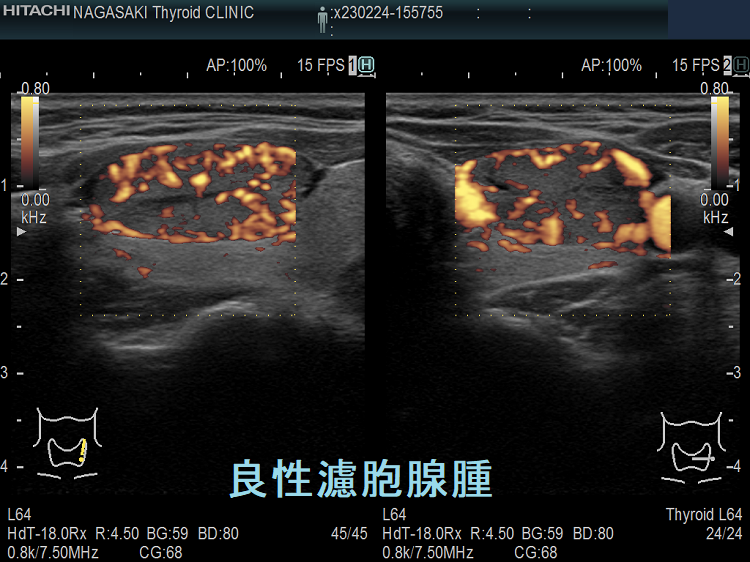

甲状腺のう胞に見えるが実は甲状腺腫瘍

甲状腺のう胞(甲状腺嚢胞)に見えるが甲状腺腫瘍 超音波(エコー)画像;低エコー(真っ黒)で、内部にコロイド様物質があるように見えるため、甲状腺のう胞(甲状腺嚢胞)と間違えます。

甲状腺のう胞に見えるが実は甲状腺腫瘍 eFlow

甲状腺のう胞(甲状腺嚢胞)でなく甲状腺腫瘍  eFlow(イー フロー);内部血流が、はっきり見えて甲状腺腫瘍なのがわかります。

たとえば、通常Bモードでは、

1. のう胞(嚢胞)に見えても、高感度パワードプラーで低流速の細い血管が検出され、実は真っ黒な(極めて低エコーな)甲状腺腫瘍 [甲状腺のう胞(甲状腺嚢胞)に見えるが甲状腺腫瘍]

2. 充実性腫瘍に見えても、高感度パワードプラーで低流速の細い血管が検出されず、実はただの甲状腺のう胞腺腫(甲状腺嚢胞腺腫)(内部の不均質な実質様エコーは粘稠なコロイド物質)

だったなど、臨床診断が覆る場合があります。特に1.の場合は、甲状腺腫瘍甲状腺のう胞(甲状腺嚢胞)と間違えると大変な事になります。極めて低エコーな甲状腺腫瘍は、甲状腺乳頭癌甲状腺濾胞癌甲状腺髄様癌甲状腺悪性リンパ腫の可能性があるからです。